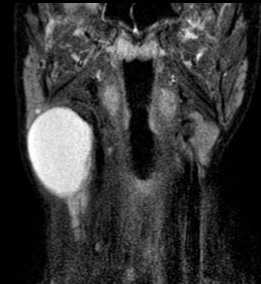

(Слева) МРТ Т1ВИ FS c КУ, коронарная проекция. В сонном пространстве определяется накапливающее контраст новообразование. В толще опухоли имеются участки кистозного перерождения, которые весьма характерны для шванном. Характерно смещение внутренней сонной артерии в медиальную сторону.

(Справа) КТ с КУ, аксиальная проекция. В надподъязычном отделе сонного пространства визуализируется шваннома, интенсивно накапливающая контраст. Внутренняя и наружная сонные артерии смещены в медиальную сторону, что характерно для шванном. Внутренняя яремная вена в редких случаях смещается кпереди. Если шваннома богато кровоснабжается, то по своему виду она может напоминать параганглиому.